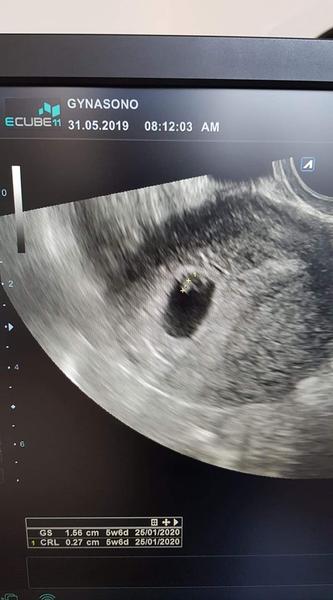

@kukurica77 😍dneska kontrola u doki mam kludovy rezim a duphaston bo som spinila trosicku. uz krasne bije srdiecko 5+6tt